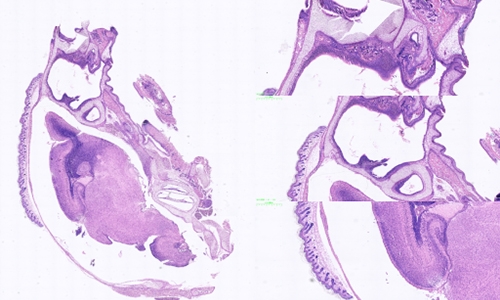

在病理学领域,HE染色(Hematoxylin and Eosin Staining)作为一种经典的染色方法,被广泛应用于组织样本的观察和分析。HE染色不仅为病

2023/12/15详情 >